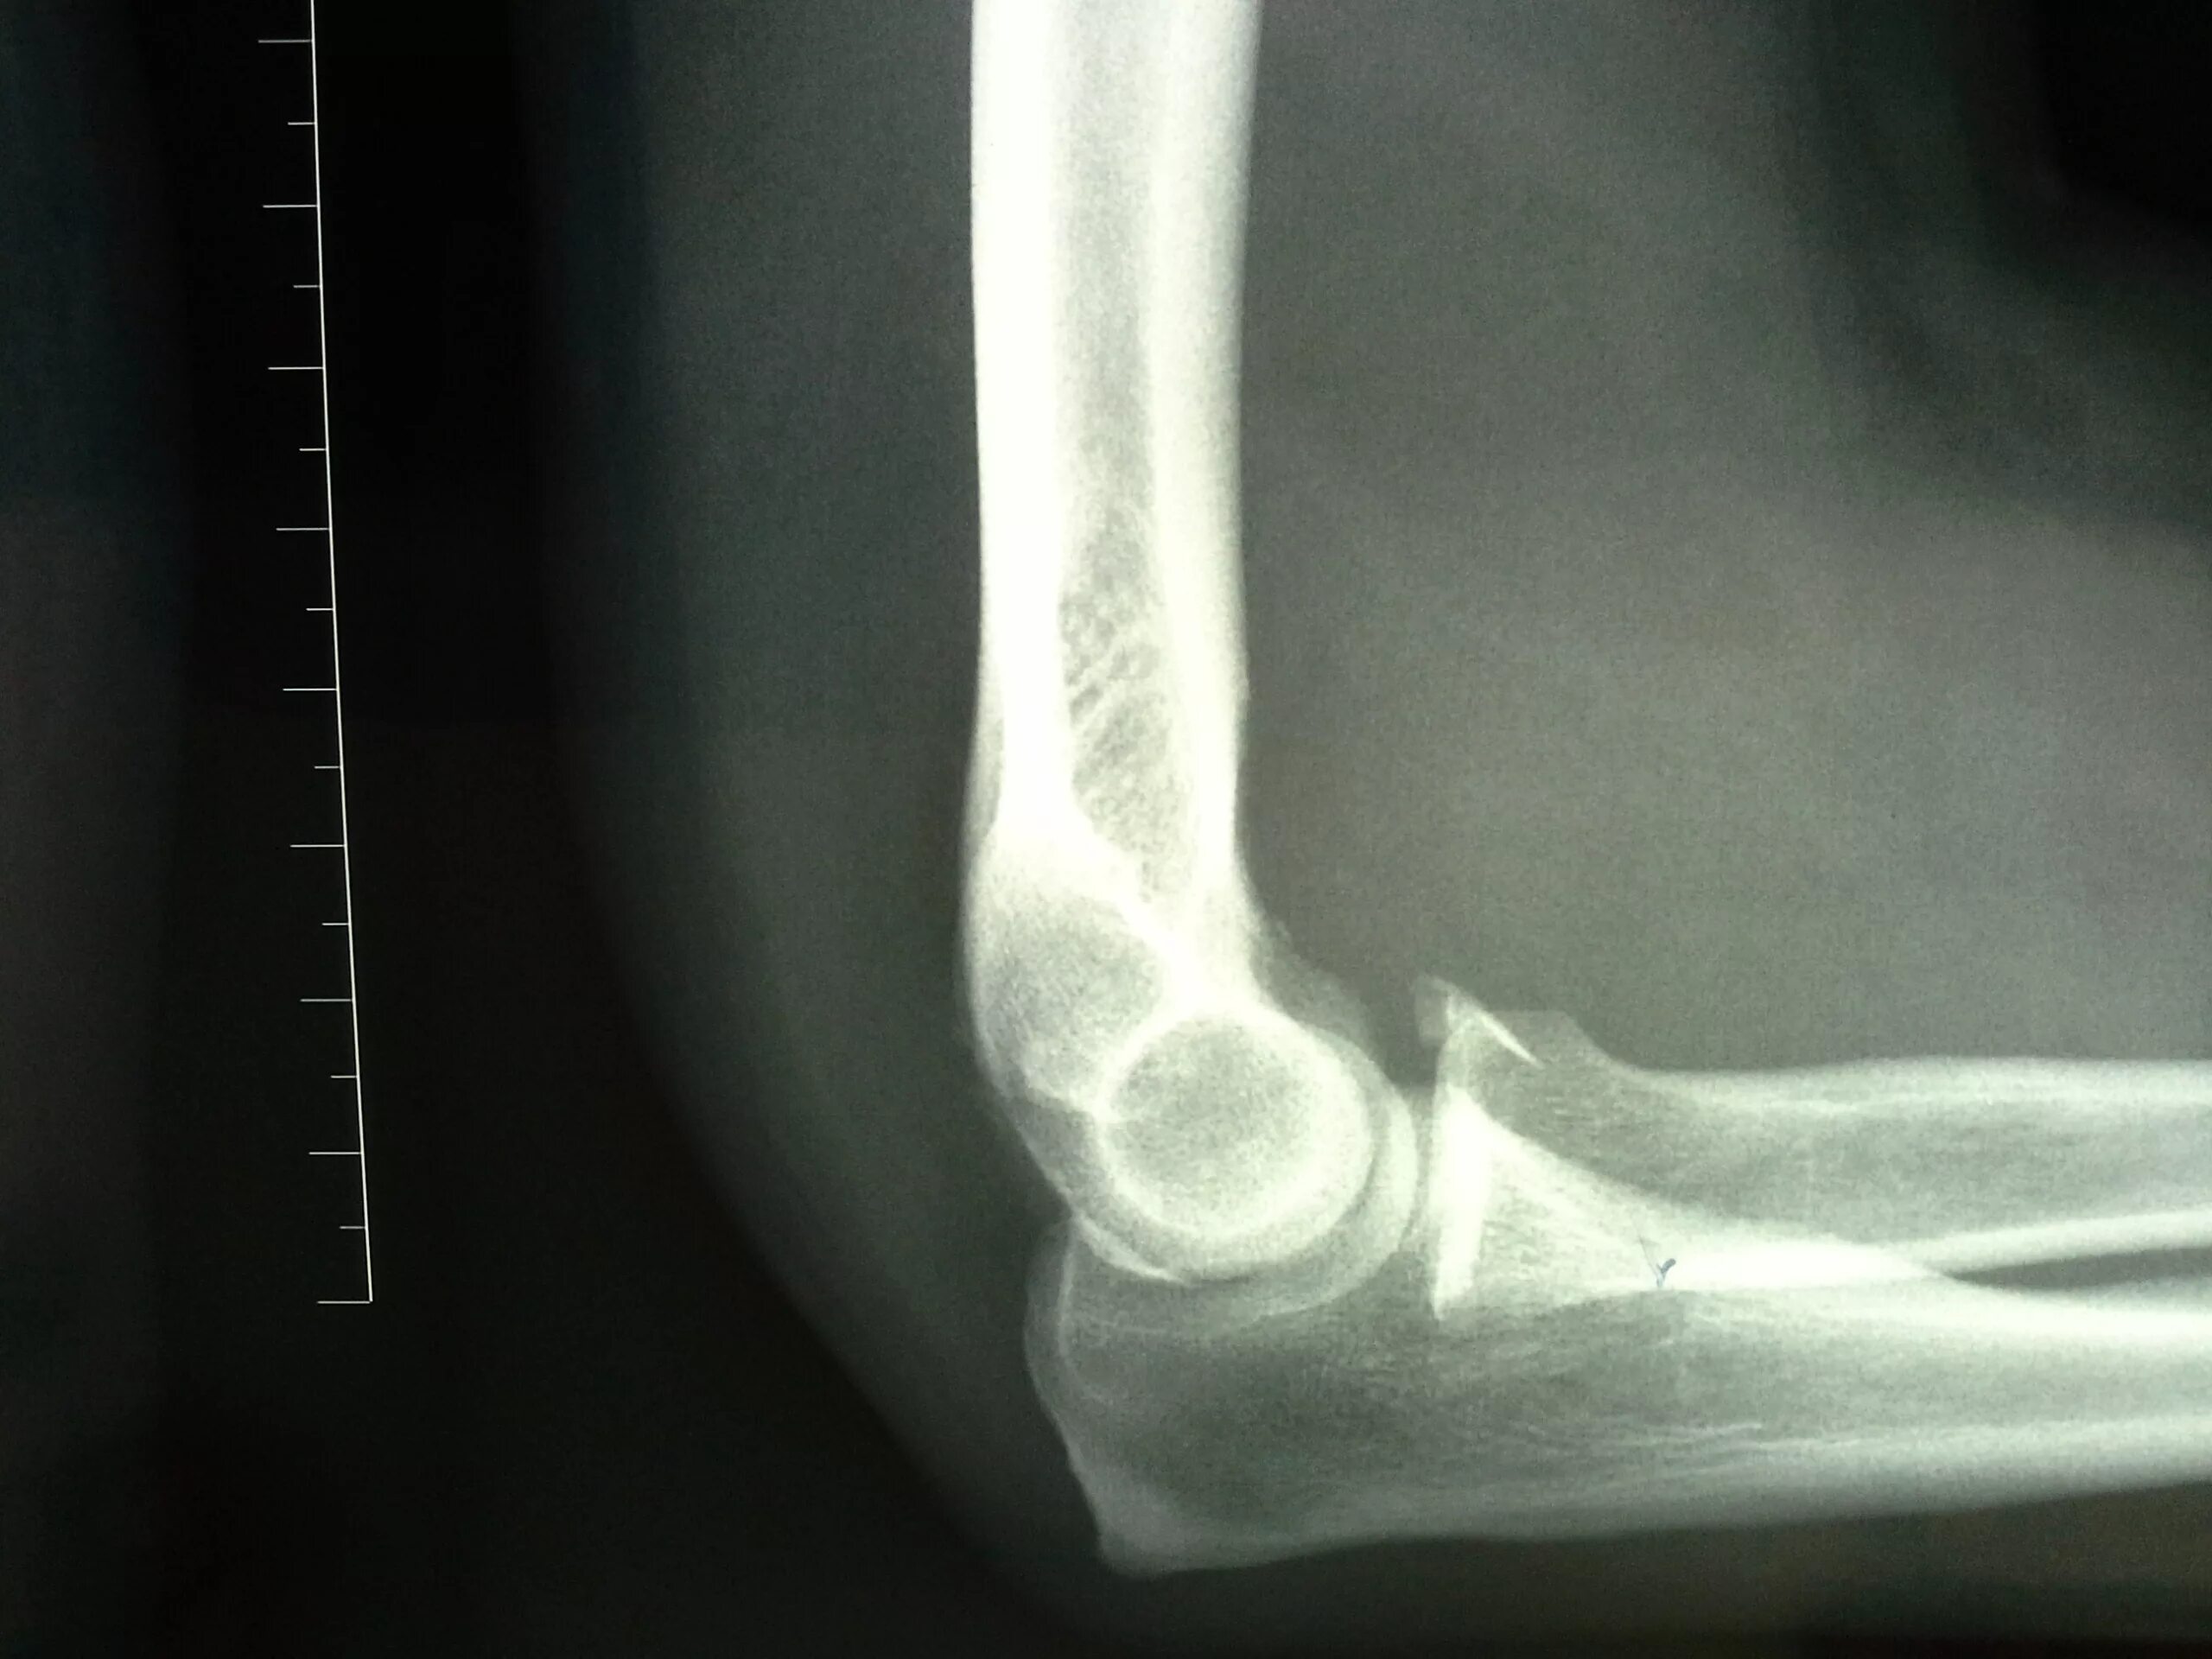

Перелом локтевой